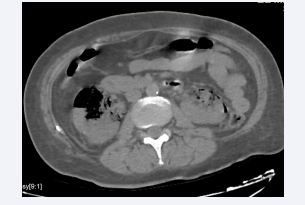

Axial section of an abdominal CT scan without intravenous  contrast injection showing a left kidney with parenchyma laminated  by hydronephrosis, with air bubbles in the parenchyma and calyces.  The appearance is compatible with a left EPN, class 2 according to  Huang et al.

Figure 3: Axial section of an abdominal CT scan without intravenous contrast injection showing a left kidney with parenchyma laminated by hydronephrosis, with air bubbles in the parenchyma and calyces. The appearance is compatible with a left EPN, class 2 according to Huang et al.